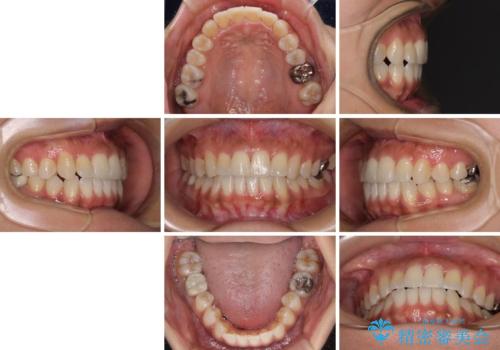

骨格的な問題を解決したことで、下顎は部分矯正で対応することができました。

上顎骨の横幅が狭く、歯列が混み合っていたため、急速拡大装置により側方拡大し、咬み合わせと歯列を改善することとしました。

下顎は部分的に咬み合わせに問題があったため、部分的な装置を付けることとしました。